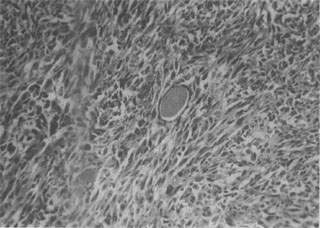

【常见的肉瘤有以下几种:】 1.纤维肉瘤(fibrosarcoma) 是肉瘤中常见的一种,其发生部位与纤维瘤相似,以四肢皮下组织为多见。分化好的纤维肉瘤细胞多呈梭形,异型性小,与纤维瘤有些相似;分化差的纤维肉瘤则有明显的异型性(图7-17)。纤维肉瘤分化好者生长慢,转移及复发较少见;分化差者生长快,易发生转移,切除后易复发。

图7-17 纤维肉瘤 瘤细胞呈梭形,体积较大,核大,核分裂像较多,具明显的异型性 2.恶性纤维组织细胞瘤(malignant fibrous histiocytoma)这是近年来才受到重视的一种恶性肿瘤,为老年人最常见的软组织肉瘤。本瘤好发于下肢,其次是上肢的深部组织和腹膜后等处,也可发生于内脏器官,但较为少见。肿瘤细胞可有多种类型,电镜下,肿瘤细胞类型的多样性理更为明显,主要为纤维母细胞和组织细胞,此外尚见原始间叶细胞、肌纤维母细胞、黄色瘤细胞和多核瘤巨细胞。异型性往往十分明显,核分裂像多见。绝大多数肿瘤可见中等量到多量的慢性炎性细胞浸润。有的区域见纤维母细胞可呈束状交织排列和(或)排列成辐状,后者被认为有一定诊断价值;有的区域多形性明显,见多肿瘤细胞混杂分布,无一定排列形式而且异型性十分突出,可见形态坚异具有丰富嗜伊红胞浆的瘤巨细胞;有的区域粘液变性明显。关于此瘤的组织发生,有研究认为是由原始间叶细胞向不同方向分化所成。此瘤的恶性程度较高,切除后易复发和转移。 3.脂肪内瘤(liposarcoma) 为肉瘤中较常见的一种类型,多发生于大腿及腹膜后的软组织深部。来自原始间叶组织,极少从皮下脂肪层发生,与脂肪瘤的分布相反。这说明脂肪肉瘤极少是由脂肪瘤恶变而来,而是一开始即具恶性特征。本瘤多见于40岁以上成人,极少见于青少年。肉眼观,大多数肿瘤呈结节状或分叶状,表面常有一层假包膜,可似一般的脂肪瘤,亦可呈粘液性外观,或均匀一致呈鱼肉样。本瘤的瘤细胞形态多种多样,可见分化差的星形、梭形、小圆形或呈明显异型性和多形性的脂肪母细胞,胞浆内可见多少和大小不等的脂滴空泡(图7-18),也可见分化成熟的脂肪细胞,并常以某种细胞成分为主。间质有明显粘液性和大量血管网形成者,称为粘液样型脂肪肉瘤。当以分化差的小圆形脂肪母细胞为主(圆形细胞型脂肪肉瘤)或以多形性脂肪母细胞为主时(多形性脂肪肉瘤),恶性程度高,易有复发和转移。